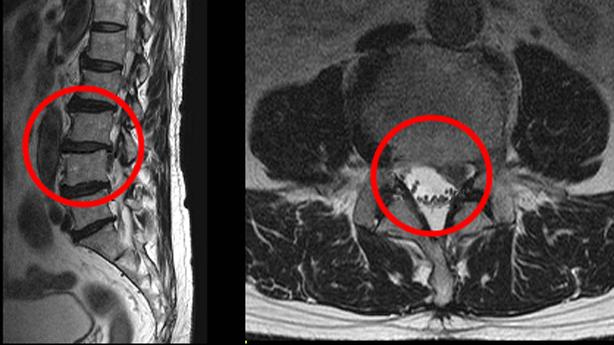

연세건우병원 이기열 원장은 "자세를 고치는 것이 가장 중요하다"며 “자세가 비뚤어진 상태로 오랜 시간 지속적인 압박을 받게 되면 척추 사이에 있는 디스크가 눌려 찌그러지면서 벌어진 쪽으로 밀려나오며 이 상태에서도 지속적으로 자극을 받게 되면 섬유테가 붓고 찢어지거나, 안에 있는 수핵이 섬유테를 찢고 터져서 밖으로 밀려 나오기도 한다”고 말했다.